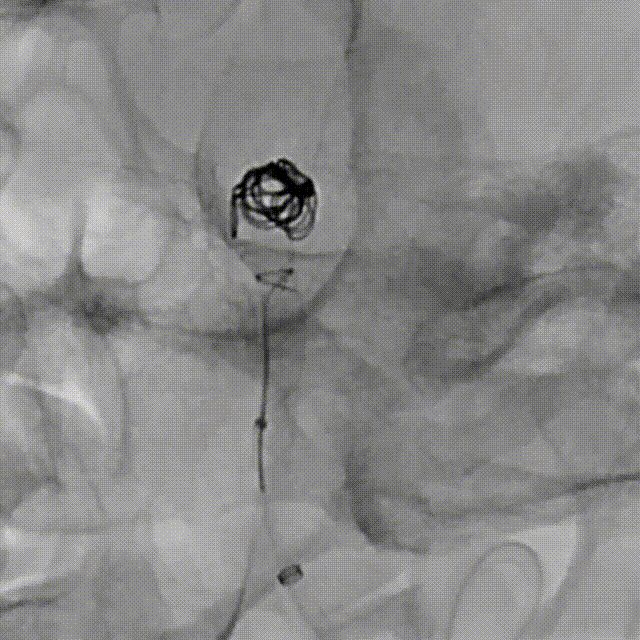

Tubridge Plus Case 2